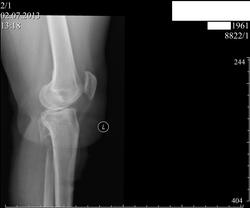

Пациентка 52 лет.Жалобы на боли в коленных суствах, больше справа, ноющие , усиливающиеся при движении. Можно ли не зная анамнеза определиться, что же было с  малоберцовой костью

Операций не было. Была травма голени, с углообразным переломом малоберцовой кости в верхней трети в 2008году (так написано в протоколе R-исследования коленного сустава). Я предполагаю, что сейчас мы видим результат неправильно лечённого перелома малоберцовой кости и не зная анамнеза разобраться в этом, практически не представлятеся возможным.Хотя Dima  и Андрей Юрьевич показали  свою сверхпрницательностьyes! Я то же, пока не прочитал запись в амбулаторной карте, предполагал , что вероятно была какая-то резекция кости.

Трактовала, как экзостоз по передней поверхности малой берцовой кости)).

Виктор Григорьевич, мне  кажется, что это ротированная головка малоберцовой кости так получается.

Александр, я о БЕДРЕННОЙ кости!...бог с ней, с малоберцовой, там теперь уже понятно)))))

yes! Кстати, у пациентки после травмы (автоаварии) развилась нейропатия малоберцового нерва!

Да, коллега вы правы.Насколко я понял было серьёзное ДТП:   последствием которого явился перелом костей голени( авария была в 2004 году); при чём при описании R-граммы коленного сустава от 2008г.отмечено, что имеет место углообразный перелом верхней трети малоберцовой кости.